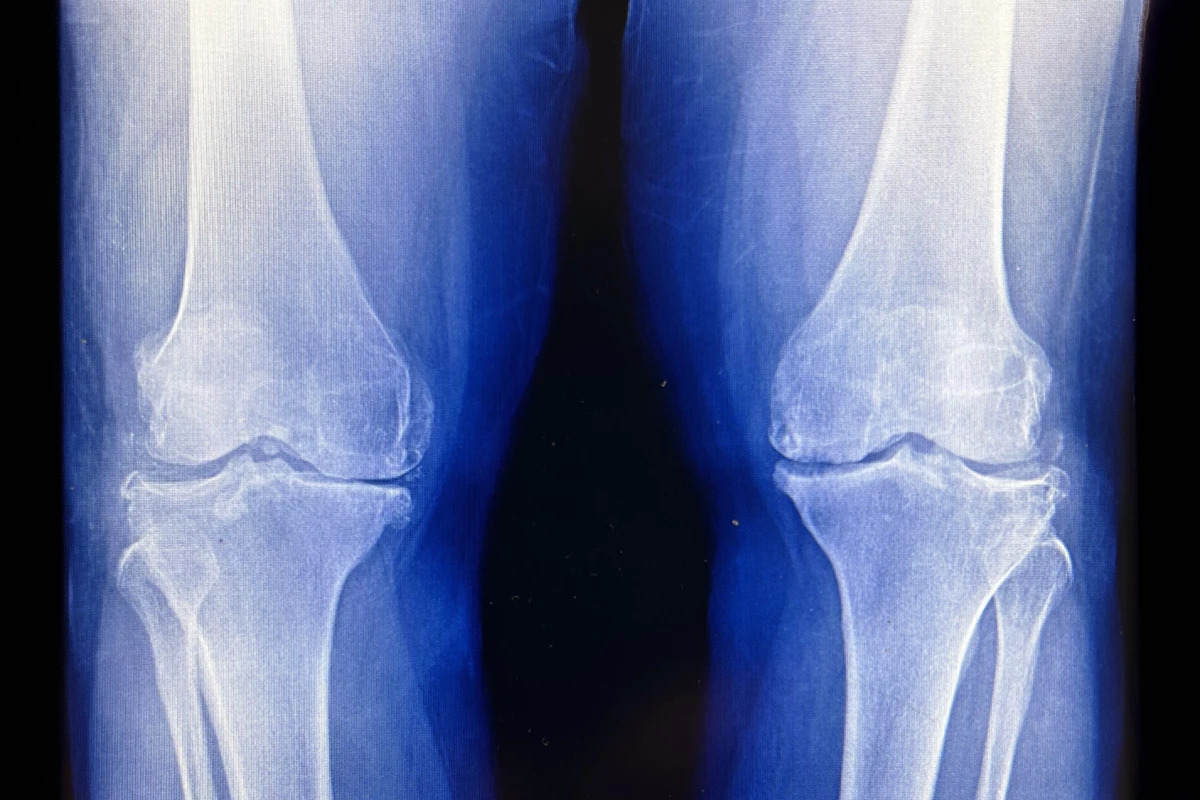

Low-dose radiation treatment may delay knee replacement surgery in people with osteoarthritis. Wikimedia Commons/NP2025 CC BY-SA 4.0 –

The trial included 114 people with primary knee OA, diagnosed by moderate damage visible on X-rays, and significant pain with walking. They were randomly assigned to one of three groups: very low-dose radiation (0.3 Gy total, spread over six sessions of 0.05 Gy), low-dose radiation (3 Gy total, spread over six sessions of 0.5 Gy), or a sham treatment that did not deliver radiation.